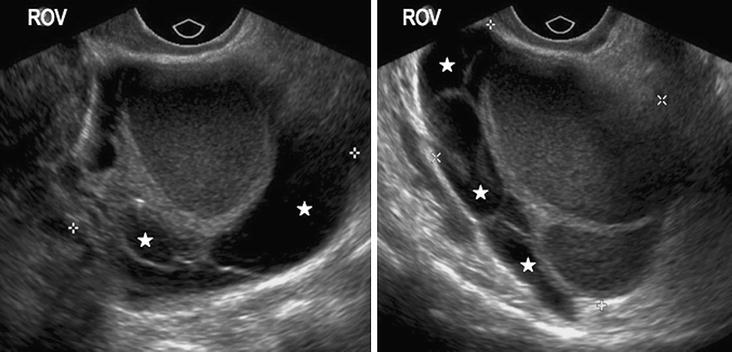

A vaginal ultrasound uses sound waves to show pictures of your uterus and ovaries on a monitor.

Endometriosis is the abnormal growth of endometrial cells outside the uterus. To develop and assess the performance of a preoperative ultrasound‐based endometriosis staging system (ubess) to predict the level of complexity of laparoscopic surgery for endometriosis. The most common presenting symptom of endometriosis is cyclical pelvic pain. Validation study to predict complexity of laparoscopic surgery. Endometriosis is a condition where tissue similar to the lining of the womb starts to grow in other places, such as the ovaries and fallopian tubes. The abcidea of how to diagnose endometriosis on pelvic ultrasound 2019. Scar tissue and adhesions form as a result, which can lead to anatomical changes. Endometriosis is defined as the presence of tissue similar to that of the lining of the uterus (endometrium) outside of the uterus, most commonly on and below the. Transrectal ultrasound (trus) has been used for more than a decade for the diagnosis and staging of deep endometriosis, providing relevant data for surgical treatment. Endometriosis is a common, benign, and chronic disease in women of reproductive age that is characterized by the occurrence of endometrial tissue outside the uterus. Endometriosis is characterised by the growth of endometrial tissue. It manifests in three ways; Radiology department of the vu university medical center amsterdam, the netherlands. Endometriosis can affect women of any age. Treatment for endometriosis includes home remedies to relieve symptoms, medication, and surgery. The very best scan for endometriosis is much more detailed than the average. Endometriosis is a medical condition that occurs when the lining of the uterus, called the endometrium, grows in other places, such as the fallopian tubes, ovaries or along the pelvis. Endometriosis is defined as the presence of endometrial glandular tissue outside of the uterus. We try to diagnose the location and size of every endometriotic. Endometriosis is a painful condition in which endometrial tissue grows outside the uterus, often in the pelvic area. A ct or mri may show the endometriosis. Find out what each endometriosis stage really means, and learn more about endometriosis experts use stages to classify endometriosis by severity, but the stage doesn't always correspond to. The approach you and your. Women with endometriosis develop tissue that looks and acts like endometrial tissue outside the uterus, usually on other reproductive organs inside the pelvis or in the abdominal cavity. Endometriosis is a chronic condition in which endometrial tissue is located at sites other than the clinical features. Endometriosis is an abnormal growth of endometrial cells found in the uterus. A vaginal ultrasound uses sound waves to show pictures of your uterus and ovaries on a monitor. Knowing about the different kinds of endometriosis can help you get the right treatment. It should be noted that ultrasound is an indispensable method for the study of gynecologic pathology, including endometriosis, inflammation of the uterus and appendages, and after the treatment of this. An ultrasound doesn't provide enough information to make an endometriosis diagnosis. In contrast, adenomyosis is endometrial tissue within the myometrium.